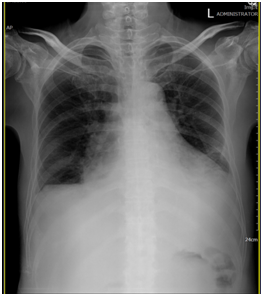

62歲退休男性,有慢性心臟衰竭及中風已四年的病史,兩腳多處潰瘍及腫痛已四個月,此次因為兩腳紅腫熱痛,懷疑蜂窩性組織炎(cellulitis)及深層靜脈栓塞(Deep vein thrombosis)而從門診收住院。理學檢查:兩小腿下1/3有色素沉著(hyperpigmentation),嚴重凹陷性水腫(pitting edema),兩小腿紅腫痛,兩足部均可摸到脈搏,在右小腿有一3*4公分的傷口,並有濕性痂皮(wet eschar),在左小腿則有一巨大的15*10公分不規則淺傷口(如圖1),並有大量滲液。胸部有呼吸喘鳴聲(wheezing),實驗室檢查:WBC: 9810, Seg:87, Hb:13.0, plate:313K, BUN/Cr:23.5/1.2, Alb:2.9, Glu:114, CRP:9.25, Alb:2.9, T4:5.07, TSH:4.0756. EKG顯示有First degree AV block. 胸部X-ray: 心臟肥大、肺水腫(pulmonary edema)並有肋膜積水(如圖2)。周邊血管超音波排除了深層靜脈栓塞,但心臟超音波: chamber dilatation and generalized hypokinesis with impair global performance with ejection fraction : 35%.顯示嚴重心臟衰竭。

圖2. cardiomegaly, pulmonary edema with pleural effusion

The 62 year-old retired male with past history of chronic heart failure and old CVA for 4years is well until 2014/12/4 when he suffered from progressive swelling, erythema, pain, tire and heat over his bilateral legs. He was admitted via OPD under the initial suspicion of cellulitis and deep vein thrombosis. Physical examination shows hyperpigmentation over lower third of both calf, severe pitting edema, swelling, erythema, tenderness over bilateral calf and palpable pulses in both feet. A ulcer about 3*4cm with wet eschar 100% over right lower leg. The other huge shallow ulcer about 15*10cm with irregular shape and heavy discharge over left calf. Wheezing in chest was also noted. Lab data shows: WBC: 9810, Seg:87, Hb:13.0, plate:313K, BUN/Cr:23.5/1.2, Alb:2.9, Glu:114, CRP:9.25, T4:5.07, TSH:4.0756. EKG: First degree AV block. Chest X-ray: cardiomegaly, pulmonary edema with pleural effusion. Pheripheral vein sono on 12/6 shows no deep vein thrombosis. Cardiac echo on 12/8 shows four chamber dilatation and generalized hypokinesis with impair global performance with ejection fraction : 35%. Then we start lasix with low dose dopamine therapy by the suggestion of CV doctor. Besides, the wounds were treated with iodosorb powder topical use, legs elevation and compression therapy with elastic bandage under the diagnosis of venous stasis ulcers. He also received an operation for debridement on 12/11 after the wheezing improved. He was discharge on 8/16.